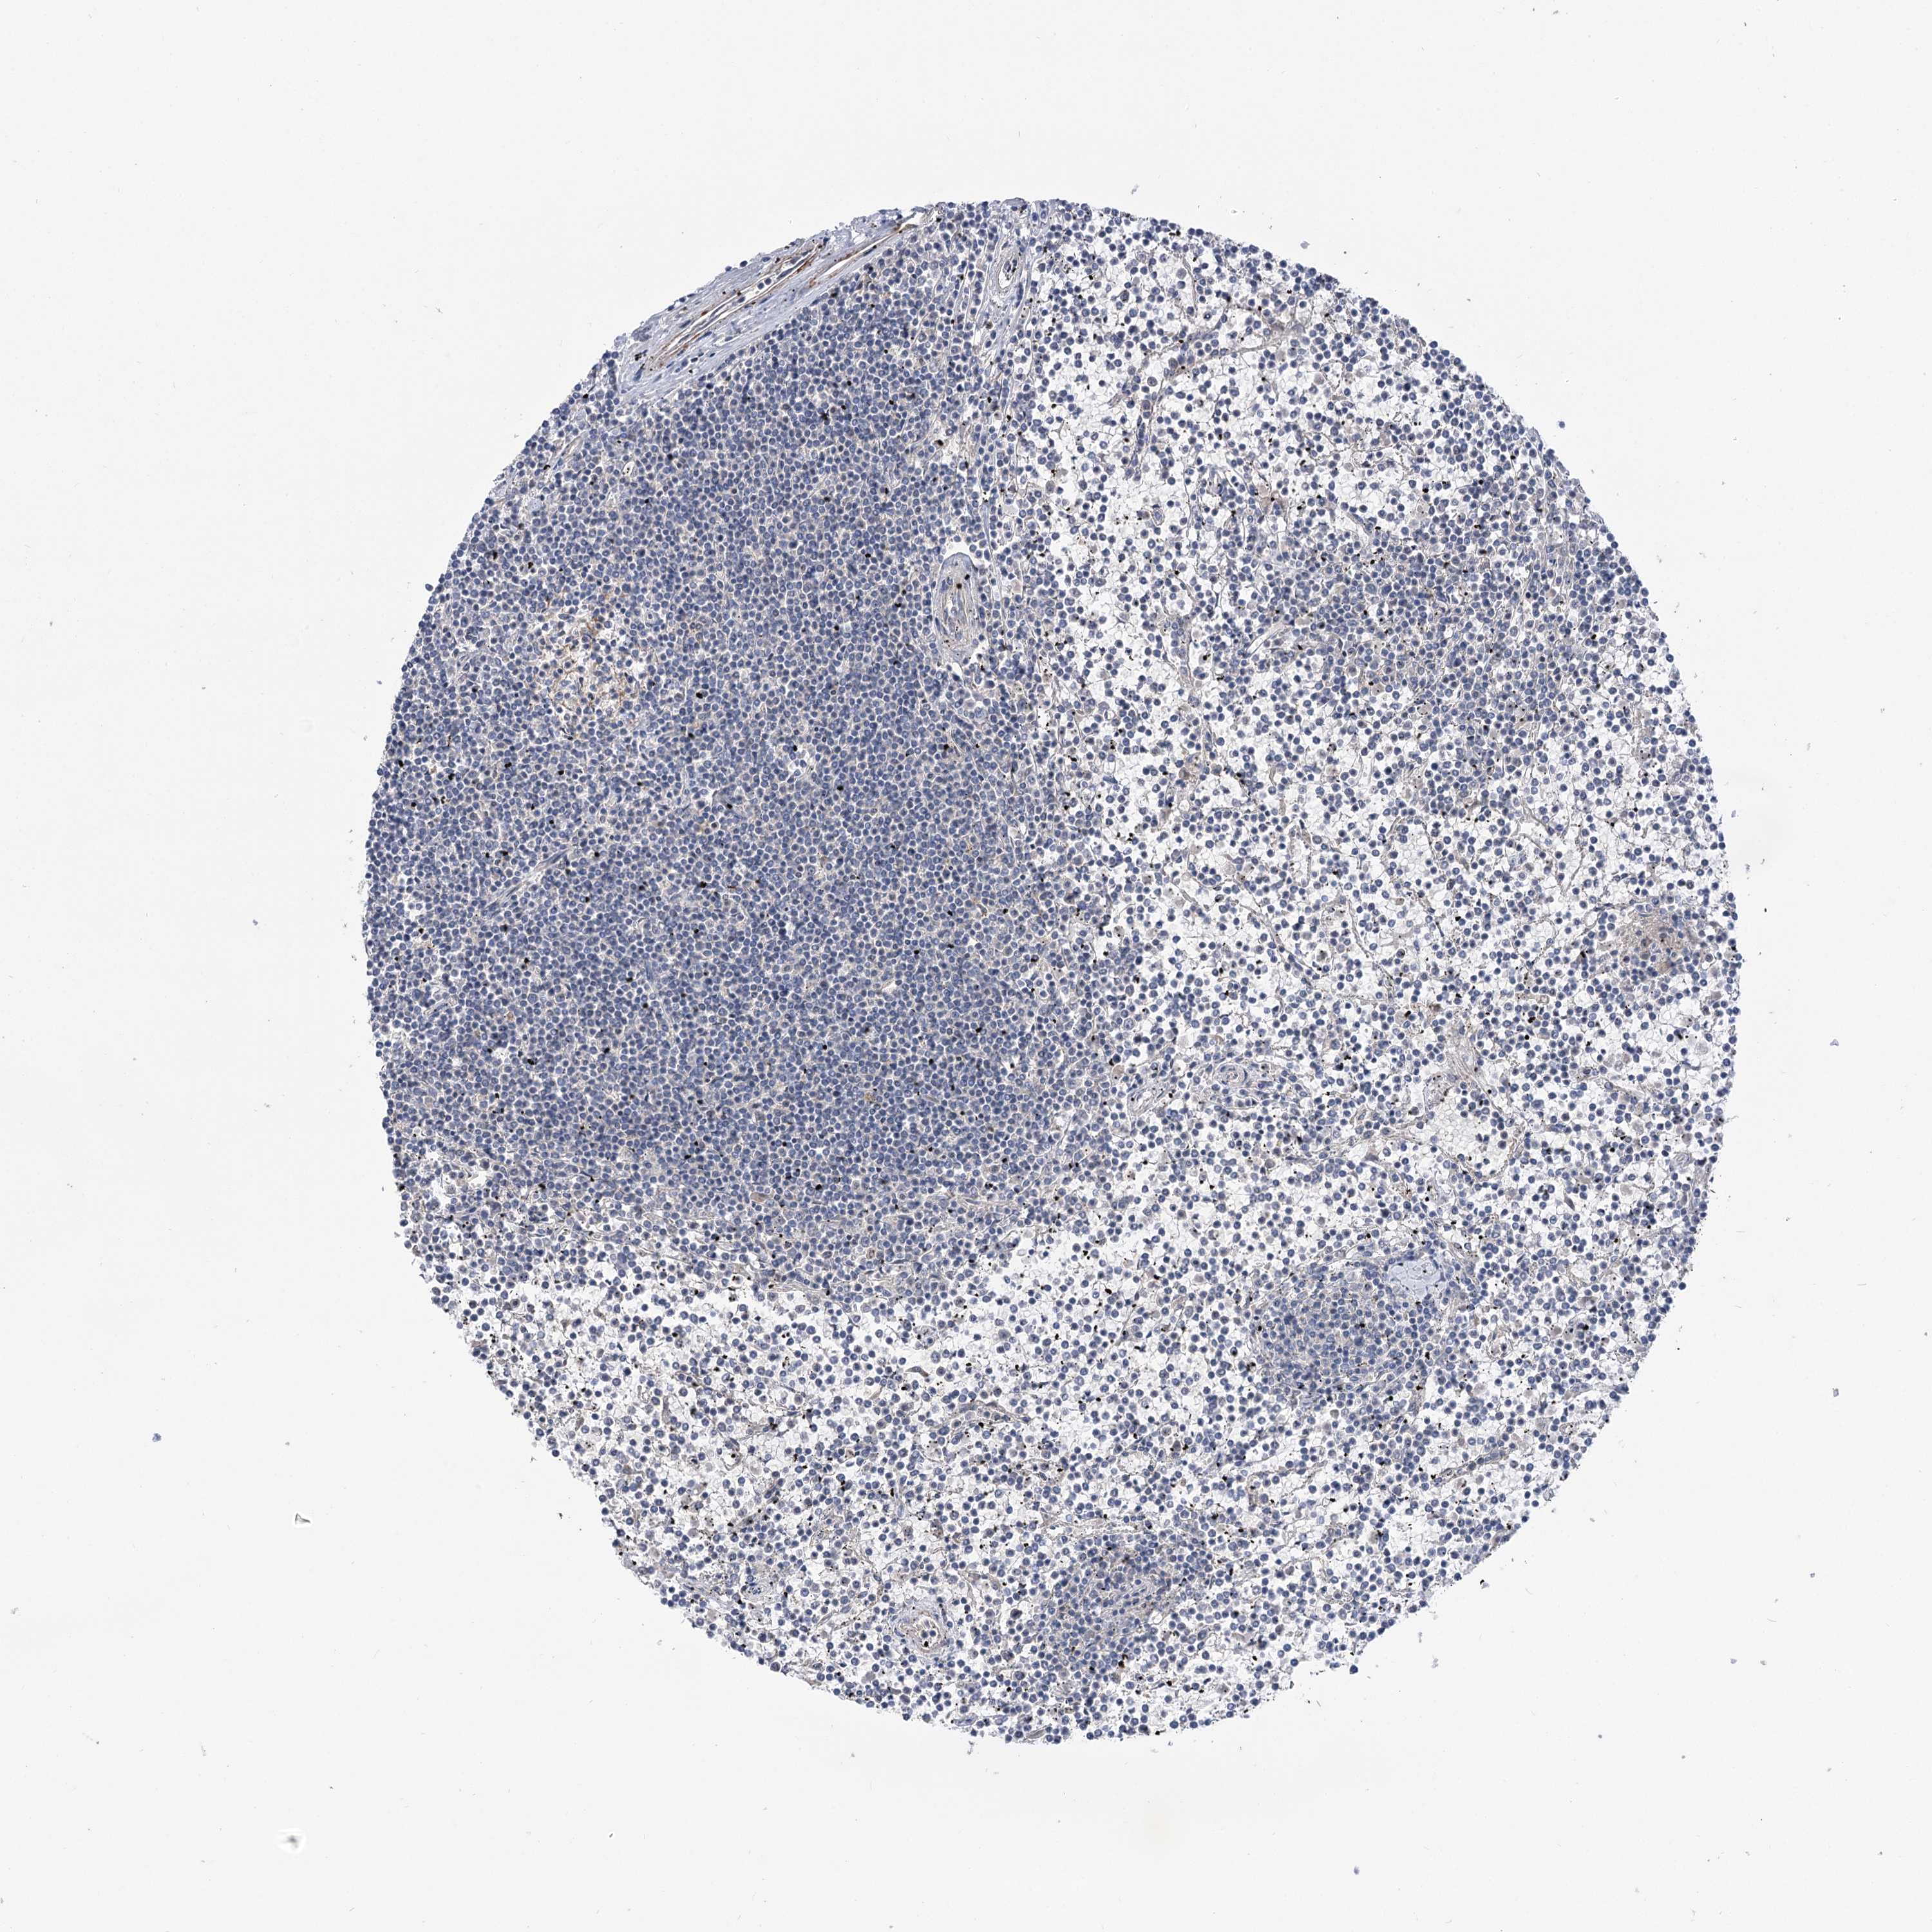

CANCER LYMPHOMA Show tissue menu

LYMPHOMA - Protein expressioni

A mouse-over function shows sample information and annotation data. Click on an image to view it in a full screen mode. Samples can be filtered based on level of antibody staining by selecting one or several of the following categories: high, medium, low and not detected. The assay and annotation is described here.

Antibody stainingi

Antibody staining in the annotated cell types in the current human tissue is reported as not detected, low, medium, or high, based on conventional immunohistochemistry profiling in selected tissues. This score is based on the combination of the staining intensity and fraction of stained cells.

Each image is clickable and will lead to virtual microscopy that enables deeper exploration of all samples and also displays staining intensity scores, fraction scores and subcellular localization as well as patient and tissue information for each sample.

Antibody HPA037759

Antibody HPA037760

Staining

High

Medium

Low

Not detected

Intensity

Strong

Moderate

Weak

Negative

Quantity

>75%

75%-25%

<25%

None

Location

Nuclear

Cytoplasmic/membranous

Cytoplasmic/membranous,nuclear

Hodgkin's disease, NOS

Malignant lymphoma, non-Hodgkin's type, High grade

Malignant lymphoma, non-Hodgkin's type, Low grade